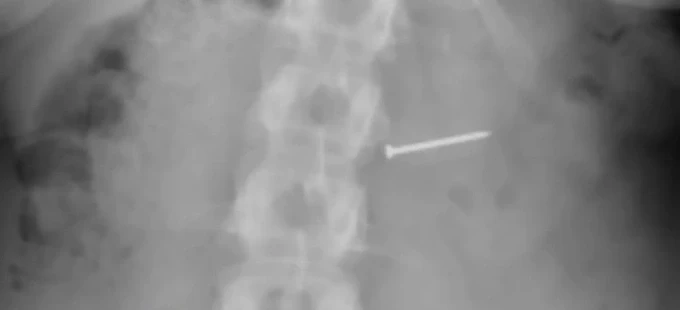

Buckley sau đó đến bệnh viện để chụp X-quang để chắc chắn thứ mình nghẹn có đúng là quả hồ đào hay không nhưng không phải. "Đó là một cái đinh. Vậy là tôi đã nuốt phải một cái đinh", cô nói.